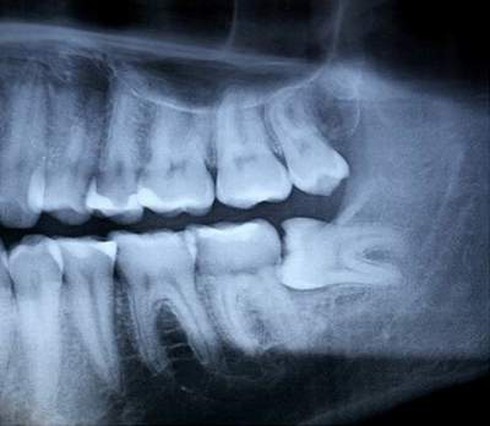

Không phải cứ khi trưởng thành bạn sẽ có răng khôn mà ước tính có khoảng 35% dân số sẽ không mọc răng khôn. Thường thì mỗi người thường có bốn răng khôn ở bốn góc hàm . Vậy câu hỏi đặt ra là với những người này răng khôn nằm ở đâu?

Thực chất lúc này răng khôn sẽ “ngoan ngoãn” nằm dưới xương hàm bình yên đến hết đời.